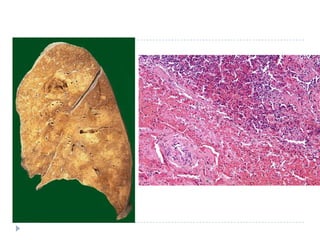

   Bronkopnömoni: yama tarzında konsolidasyon

   Lober pnömoni: bir lobun tamamının tutulumu

   Konjesyon

   Kırmızı hepatizasyon

   Gri hepatizasyon

   Rezolüsyon

LOBER PNÖMONĠ

BRONKO

PNÖMONĠ

Toplum içinde edinilenakut pnömoni morfoloji  Bronkopnömoni: yama tarzında konsolidasyon  Lober pnömoni: bir lobun tamamının tutulumu  Konjesyon  Kırmızı hepatizasyon  Gri hepatizasyon  Rezolüsyon  *Klinik açıdan önemli olan etkenin belirlenmesi ve hastalığın yayılımının belirlenmesidir